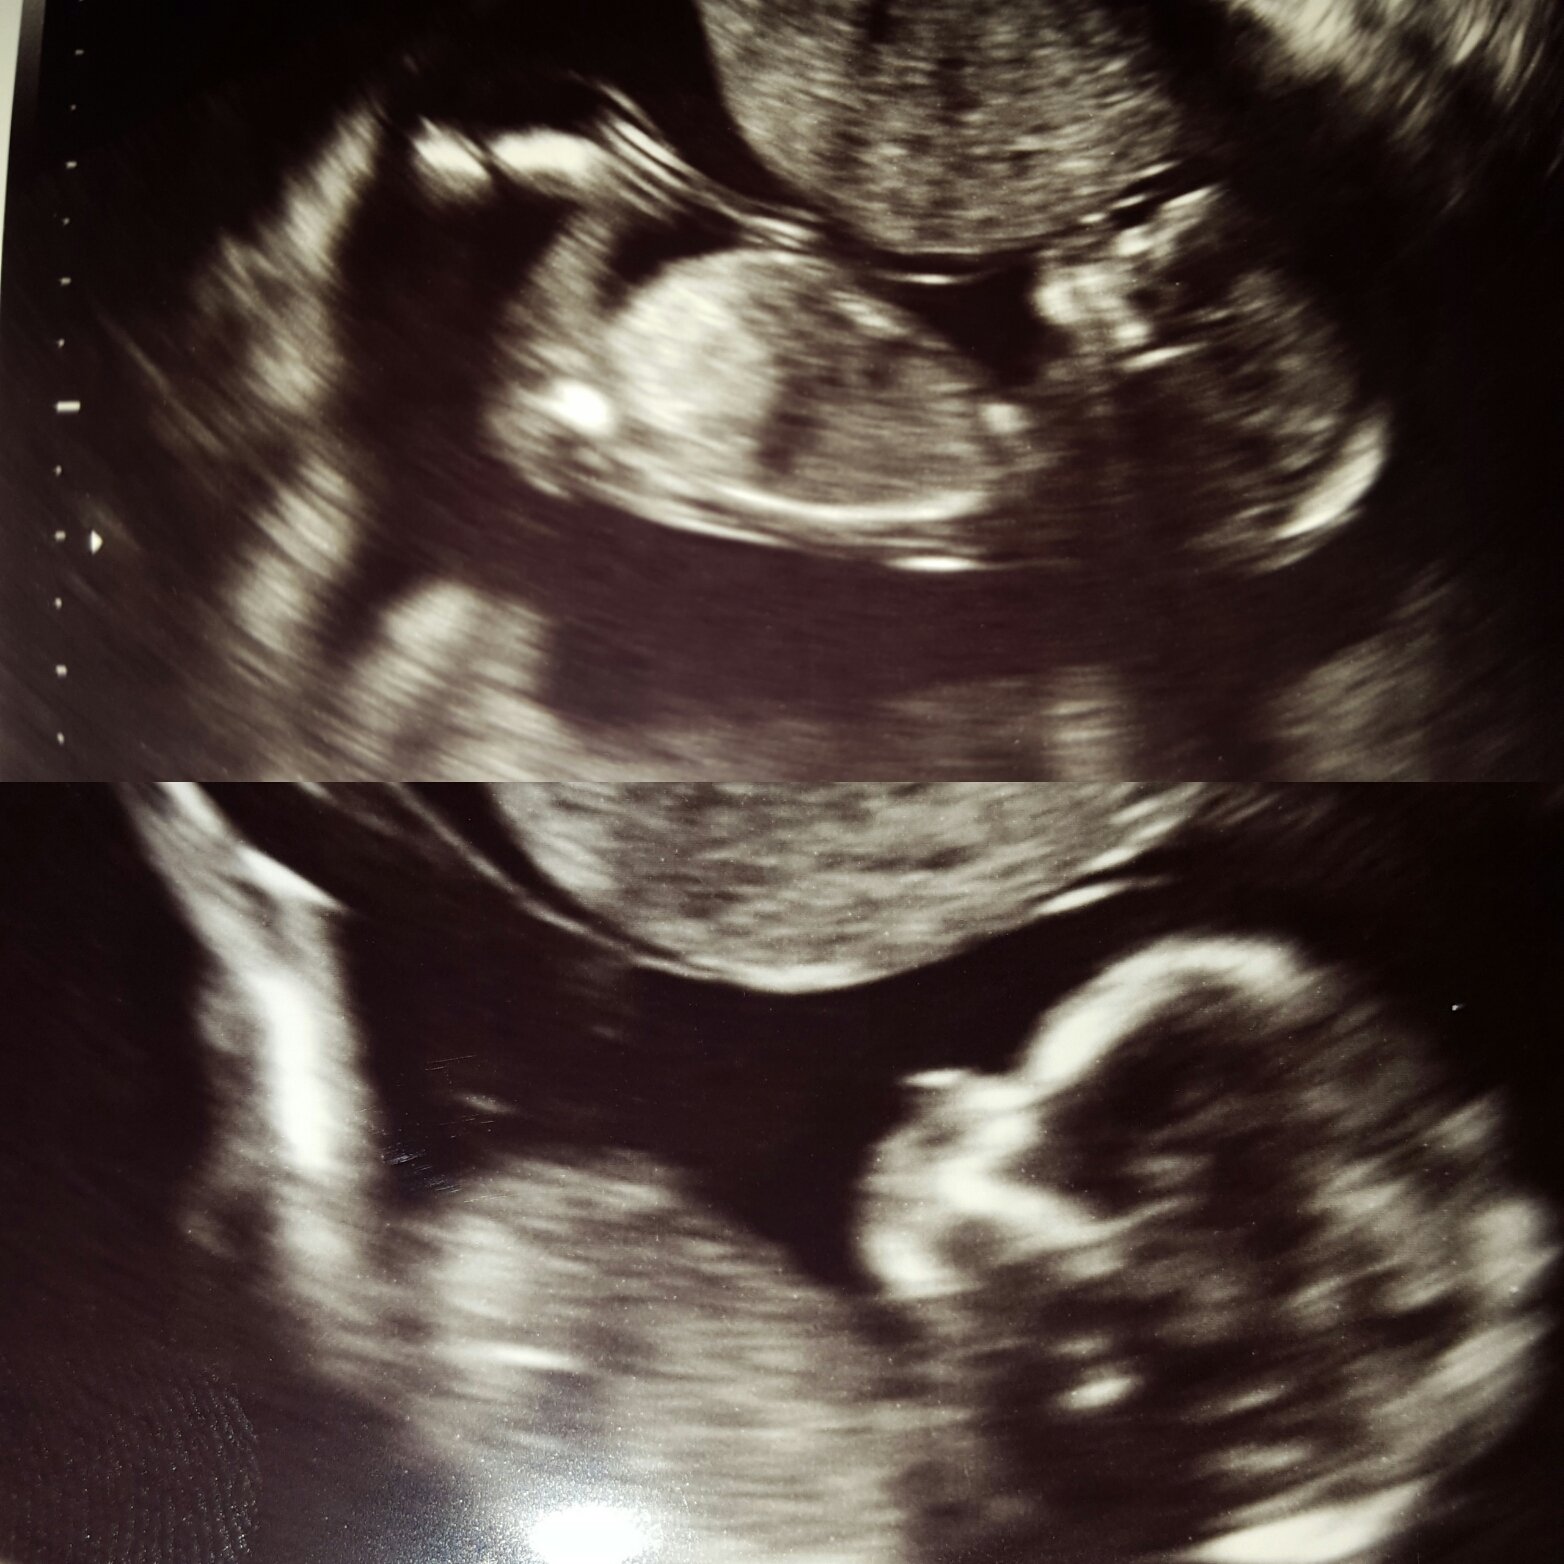

I am 13 weeks and tech thinks for sure boy, and I admit I seen what I am pretty sure were boy parts that looked very similar to my LO ultrasounds but I am still kind of ify... do you think its possible the baby could still be a girl? I would be just fine with a boy just worried about telling people we are having a boy... haha

But yeah, let me go ahead and make a guess of the sex of your baby based on a profile shot.